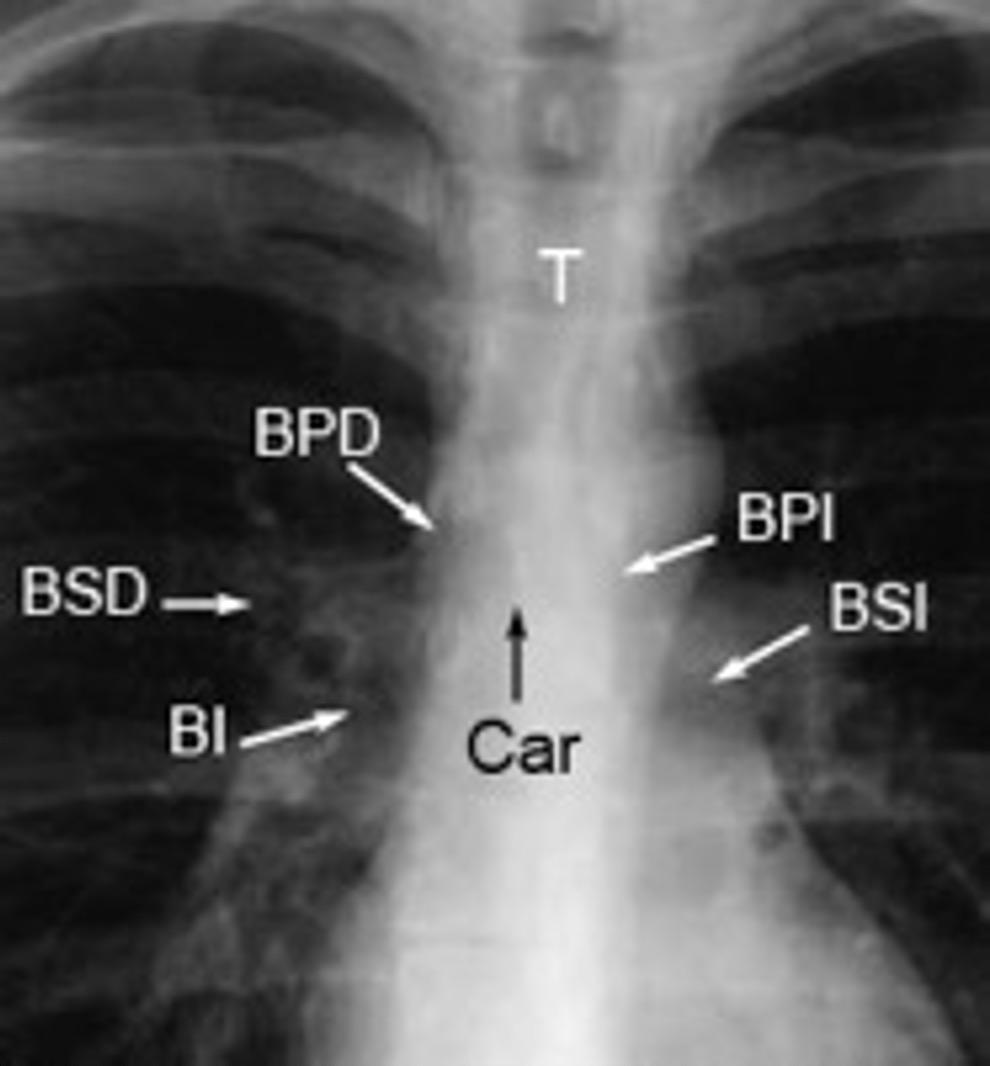

Línea paratraqueal derecha

Línea paratraqueal izquierda

Espacio subcarinal

Línea para-aórtica

Líneas paraespinales

Banda traqueal posterior

Banda retroesternal

Triángulo de Raider

Marano M et al. Cardiac Silhouette Findings and Mediastinal Lines and . Chest 2011.

Pedrosa C y Cabeza B. El Mediastino en Pedrosa C. Diagnóstico por la Imagen. Mc Graw-Hill. Interamericana.1997

Bronquio intermediario

2. Línea PARAespinal